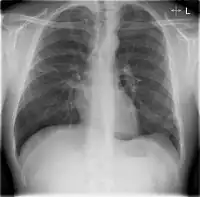

Chest X-rays of a CAP patient before (left) and after treatment

CAP is treated with an antibiotic that kills the infecting microorganism; treatment also aims at managing complications. If the causative microorganism is unidentified, which is often the case, the laboratory identifies the most effective antibiotic; this may take several days.